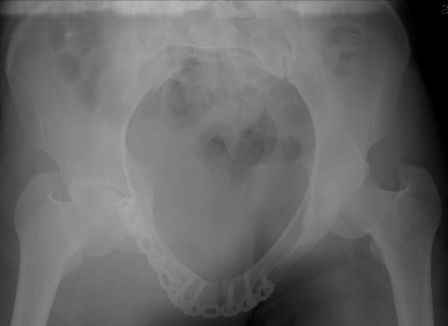

Считаю целесообразным наложить стержневой аппарат, который скорее всего позволит устранить большинство смещений и возможно станет окончательным видом лечения

IMG_0129.JPG

214KB (219953 bytes)